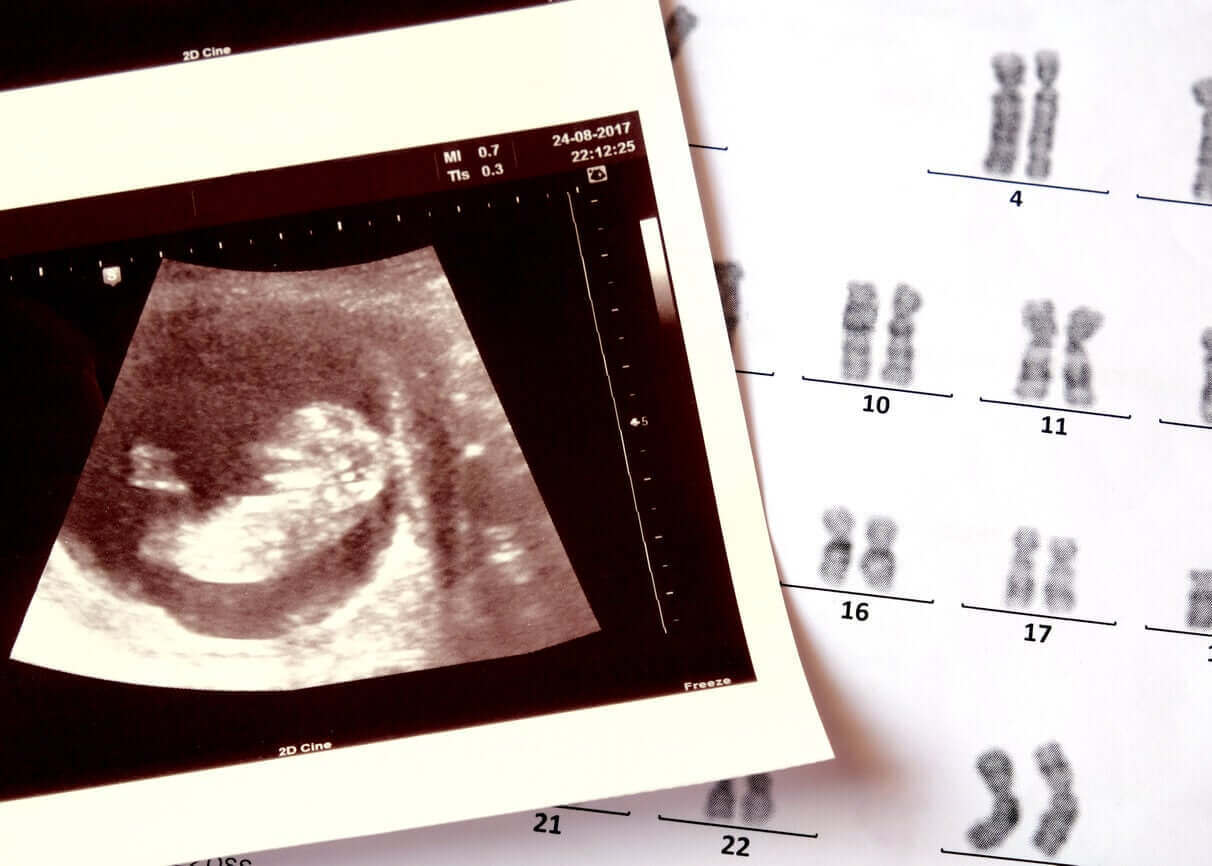

Når en fødselslege fastslår at en nåværende graviditet har høy risiko for genetiske sykdommer, kan de velge å utføre forskjellige diagnostiske studier. Blant dem, morkakeprøve, som er en prosedyre som innebærer å skaffe celler fra et lag av morkaken: fostervevet. Den brukes til å analysere babyens DNA for å diagnostisere mulige endringer i genene fra begynnelsen av svangerskapet.

En korionbiopsi er en invasiv prenatal test, ettersom det krever innsamling av en prøve av placenta chorionic villi gjennom en kirurgisk prosedyre.

Chorion er den ytre membranen som omgir fosteret i livmoren og har små villi eller fremspring av morkakevev. Både dette laget og babyen har den samme genetiske informasjonen.

- Fetal karyotype: Hver av kromosomene som inneholder den genetiske informasjonen analyseres for å finne ut antallet og strukturen til hver enkelt.

- Barnets kjønn: Takket være karyotypen er det mulig å finne ut kjønnet til babyen gjennom analysen av kjønnskromosomene.

- Kromosomavvik som Downs eller Edwards syndrom) og genetiske abnormiteter (for eksempel cystisk fibrose).